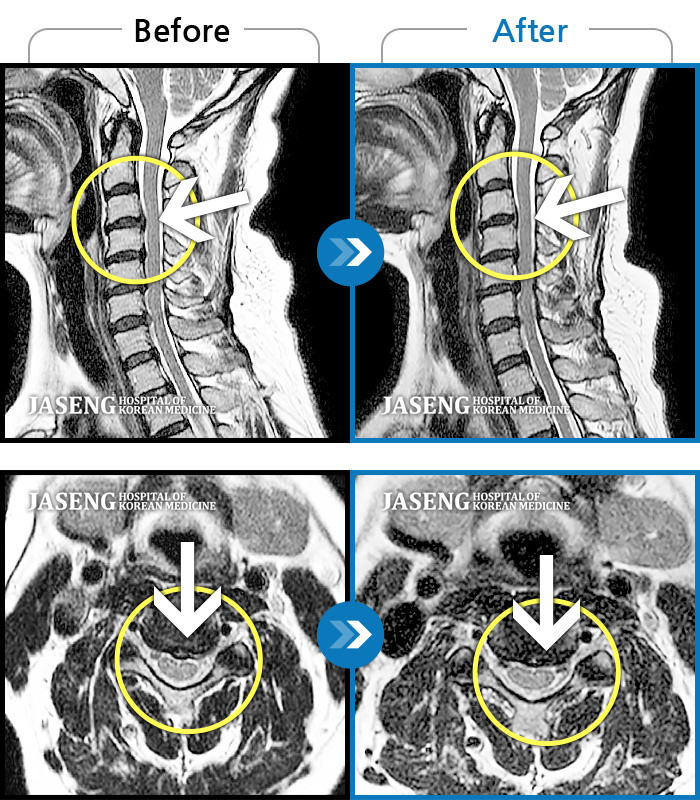

MRI 결과는 추간판협착증 2군데와 추간판탈출되어 터져서 디스크가 좌측으로 흘러내려 좌측 신경을 넓게 누르고 있는 곳이 1군데로 예상보다 심각한 상태였더군요.